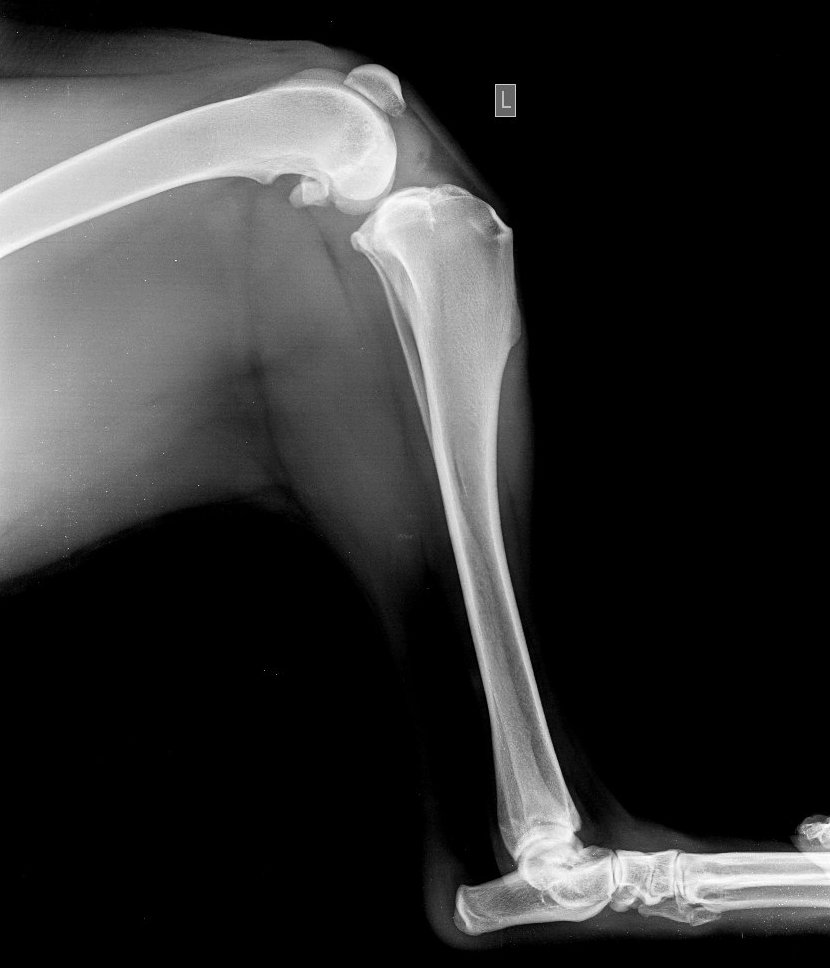

Разрыв ПКС у йоркширского терьера